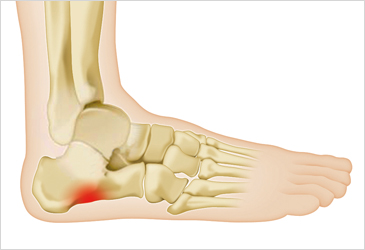

발바닥통증의 원인 발목 염좌

- 발목을 삐거나 부상을 당했을 경우, 발바닥에 통증이 나타날 수 있습니다. 이 경우에는 발목 주위의 부기나 통증이 함께 나타나는 것이 일반적입니다. 발목의 안정성이 떨어지면 발바닥에도 불편함이 전해질 수 있습니다.